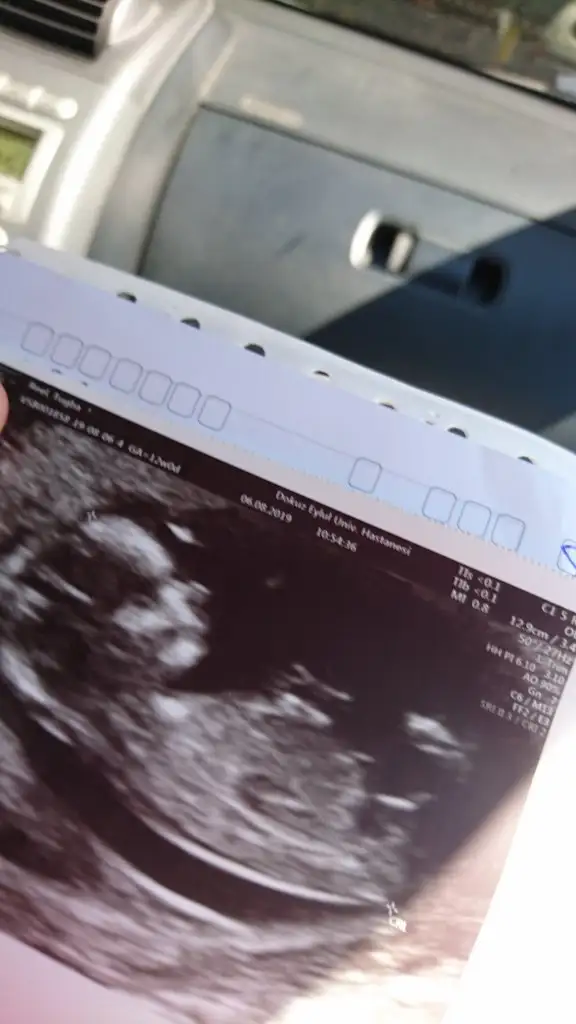

ben bugün doktora gittim geçen haftaki çıkıntıyı göremiyorum dedi.. erkek diye değerlendiriyorum demişti geçen hafta ama şimdi de karışabilir bu haftalarda anlaşılmaz falan dedi..

şaşkınlık içindeyim..

madem karışır ne diye tahmin edip fikir beyan edersin.

bu hafta usg vermedi..

geçen haftaki usg ler.. 11+2

Bence kız bu minnoş çok dik degil paralelde degil pozisyonla alakalı değilse kız diyorum

Karşıya balıyor nubu kaç haftalık usg başka varmı usg dik değil paralelde böyle usg ler beni yanıltıyor